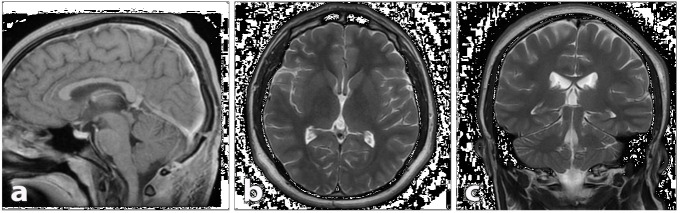

Pineal cysts (PCs) are common findings on (Magnetic resonance Imaging) MRI, often incidental in females and asymptomatic throughout life. Rare complications, like pineal apoplexy with acute hydrocephalus, require differential diagnosis and urgent intervention. We report a 19-year-old male with a progressive headache and visual decline. MRI showed a 2.3 cm pineal cyst with hemorrhagic features (apoplexy) causing hydrocephalus. He underwent endoscopic third ventriculostomy and microsurgical resection, both successful. Postoperatively, symptoms resolved completely. Though often benign, complicated PCs can be life-threatening. This case highlights their management, aiding understanding of etiologies, differential diagnoses, and treatments, enhancing medical knowledge.